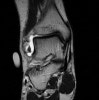

MRI : 발목 염좌(Lateral ankle sprain)